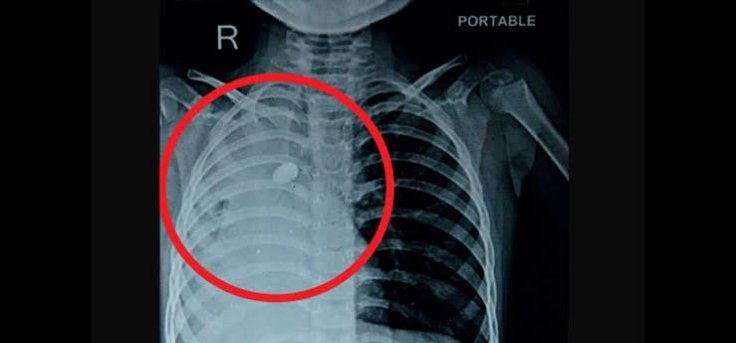

ऋषिकेश : सांस की नली में रोढ़ी बजरी की गिट्टी फंसने से एक 7 वर्षीय बच्चे की जान पर बन आई। मासूम का जीवन बचाने के लिए माता-पिता उसे लेकर कई अस्पतालों में गए, मगर मामला गंभीर देख सभी ने हाथ खड़े कर दिए। ऐसे में जोखिम उठाते हुए एम्स के चिकित्सकों ने इलाज की उच्च तकनीक का उपयोग किया और सांस की नली से होते हुए फेफड़े में फंसी गिट्टी को बाहर निकालने में कामयाबी हासिल की। बताया गया कि यह गिट्टी खेल-खेल में बच्चे के गले से नीचे उतरकर सांस की नली में फंस गई थी।

इस बाबत जानकारी देते हुए पल्मोनरी मेडिसिन विभाग के एडिशनल प्रोफेसर डॉ. मयंक मिश्रा ने बताया कि टीम वर्क से संपन्न की गई इस प्रक्रिया से चिकित्सकों की टीम, बच्चे की श्वास नली में फंसी गिट्टी को बाहर निकालने में सफल रही। डॉ. मयंक ने बताया कि निकाली गई गिट्टी का साईज 1.5×1 सेमी. था। 16 जुलाई को ब्रोंकोस्कॉपी की प्रक्रिया संपन्न करने के बाद स्वस्थ होने पर बच्चे को पिछले सप्ताह एम्स से डिस्चार्ज कर दिया गया।